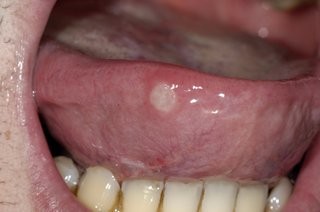

Biofilms are a collective of one or more types of microorganisms that can grow on many different surfaces. Microorganisms that form biofilms include bacteria, fungi and protists.

One common example of a biofilm dental plaque, a slimy buildup of bacteria that forms on the surfaces of teeth. Pond scum is another example. Biofilms have been found growing on minerals and metals. They have been found underwater, underground and above the ground. They can grow on plant tissues and animal tissues, and on implanted medical devices such as catheters and pacemakers.

Oral biofilm is medically important because it has broad implications for maintaining not only oral health but also systemic health. It is estimated that biofilms account for over 80% of microbial infections in the body. Research has undoubtedly shown that biofilm-dependent infections, including oral diseases such as caries, and periodontal and endodontic disease, thus pose major public health and cost concerns globally.

Periodontal disease, in particular, is considered one of the most prevalent diseases worldwide, affecting up to 50% of the world’s adult population, according to FDI World Dental Federation. Previous research has established connections between periodontal disease and preterm births, low birthweight, diabetes, and risk factors associated with cardiovascular disease and stroke. Globally, periodontitis is responsible for an estimated US$54 billion per year in lost productivity and a major portion of the US$442 billion spent annually on oral disease, according to the European Federation of Periodontology.